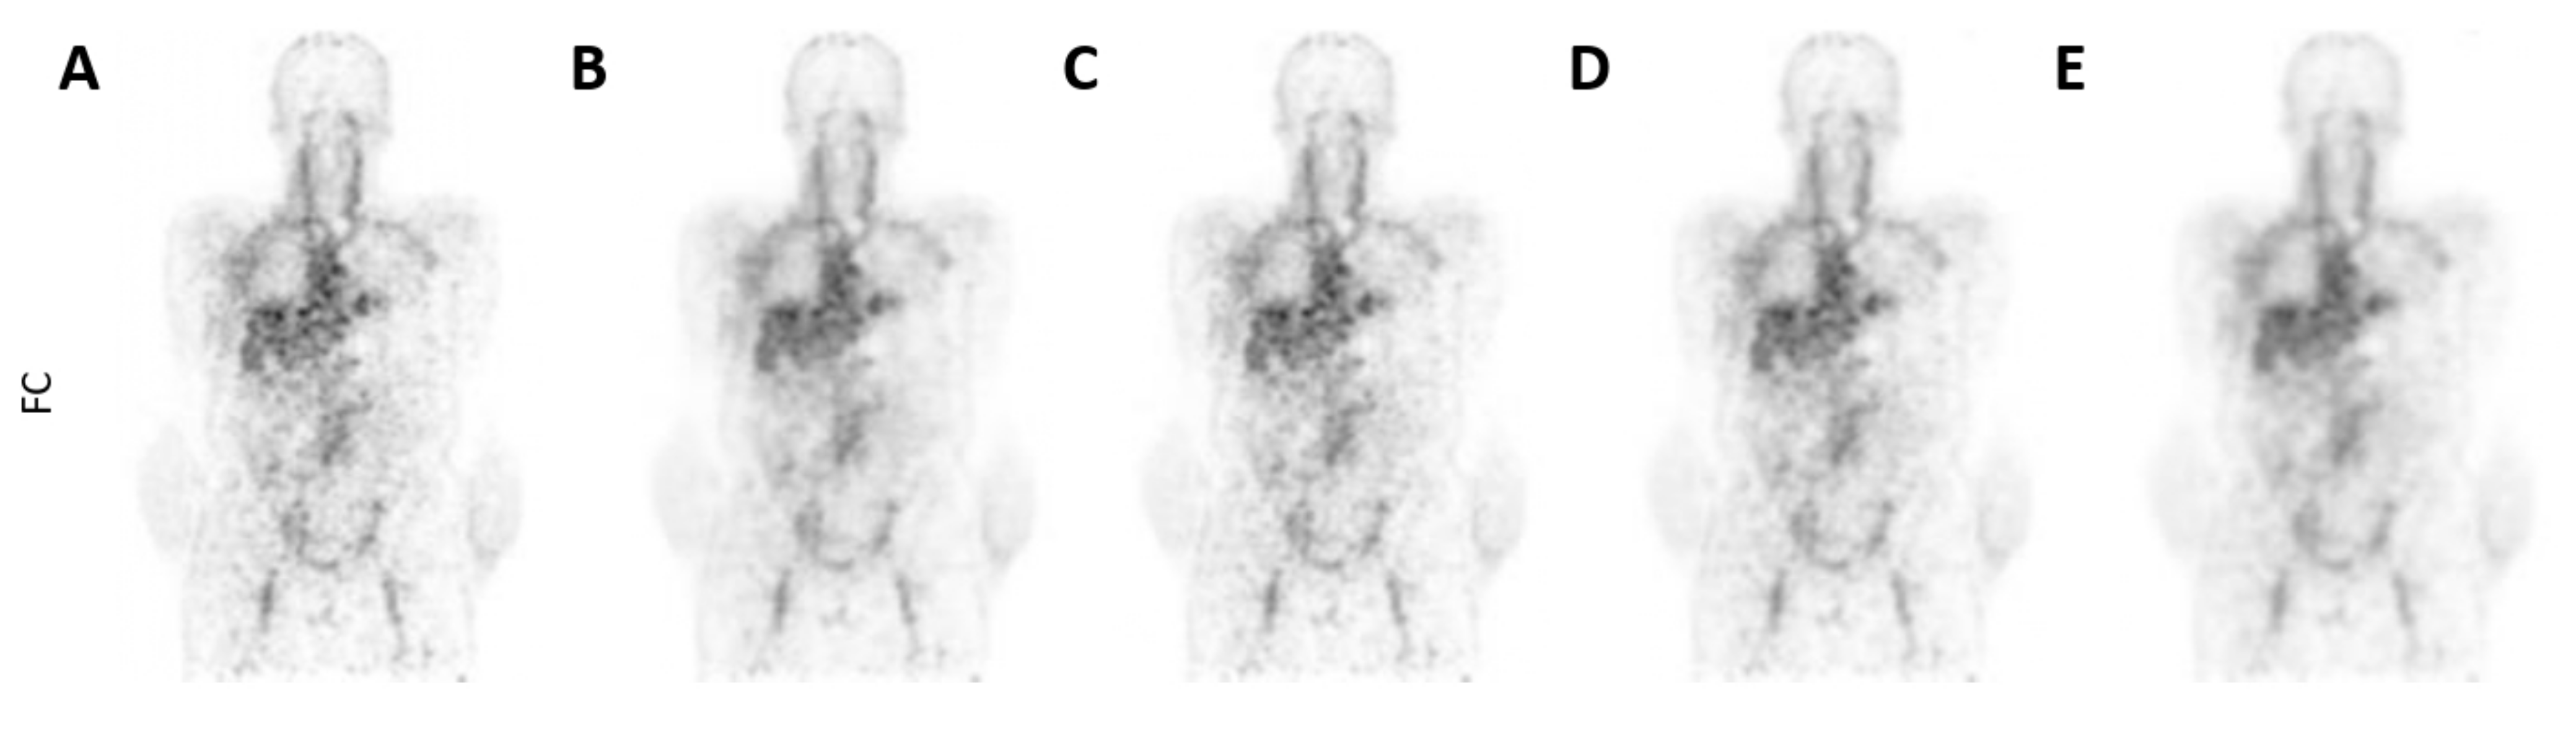

| Metrics [1–5: Low–High] | SLC-CNN | BF-2 mm | BF-3 mm | BF-4 mm | FC |

|---|---|---|---|---|---|

| Level of noise | 2.4–2.6 | 3.8–4.6 * | 2.8–2.6 | 1.4–1.2 * | 4.6–4.8 * |

| Tumour detectability | 3.4–3.8 | 4.4–4.0 * | 2.4–2.4 * | 1.4–1.4 * | 4.6–4.2 * |

| Overall scan quality | 3.8–3.8 | 3.6–3.8 | 3.4–3.0 * | 2.0–1.4 * | 3.4–3.0 * |

| Clinical acceptable? [%] | 100–100 | 100–100 | 80–80 | 0–0 * | 80–80 |

| Best scan (1/2/3/4/5) | 1–1 | 3–2 | 2–4 | 4–5 | 3–3 |